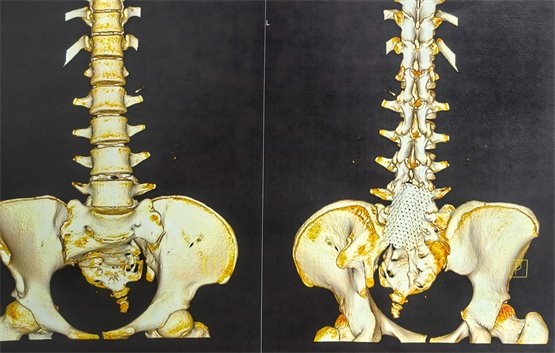

圖2為此次手術(shù)前復(fù)查腰骶椎MR檢查,提示脊髓拴系松解滿意

圖3為此次骶神經(jīng)電刺激穿刺前骶椎CT三維成像,可見骶椎裂,且骶椎扭轉(zhuǎn)畸形,根據(jù)片子可見,手術(shù)穿刺風(fēng)險(xiǎn)及難度明顯增大